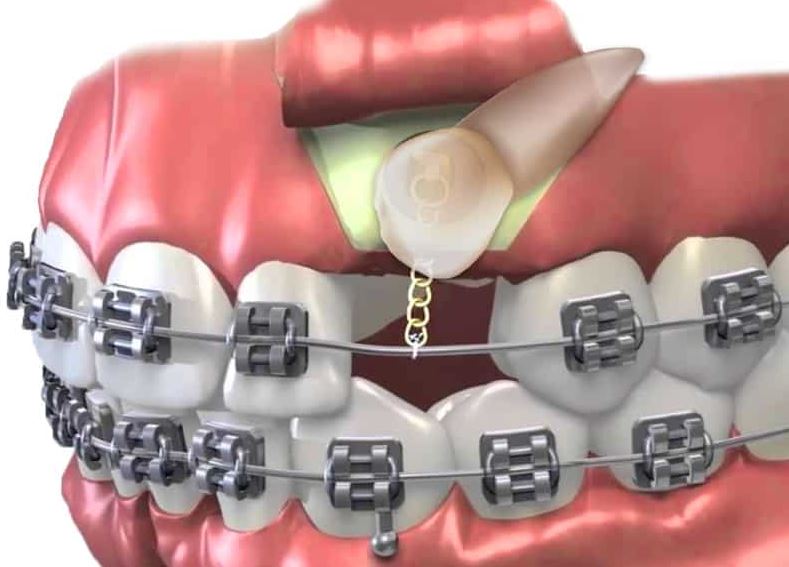

In cases where an impacted tooth doesn’t erupt on its own, a collaborative approach between an orthodontist and an oral surgeon is used. The surgeon will surgically expose the tooth and attach a bracket and chain to it. The orthodontist then applies gentle traction over time to guide the tooth into position.

The goal is to bring the impacted tooth into the dental arch, not remove it. After the tooth erupts, minor gum surgery may sometimes be needed to improve the health or appearance of the surrounding tissue.